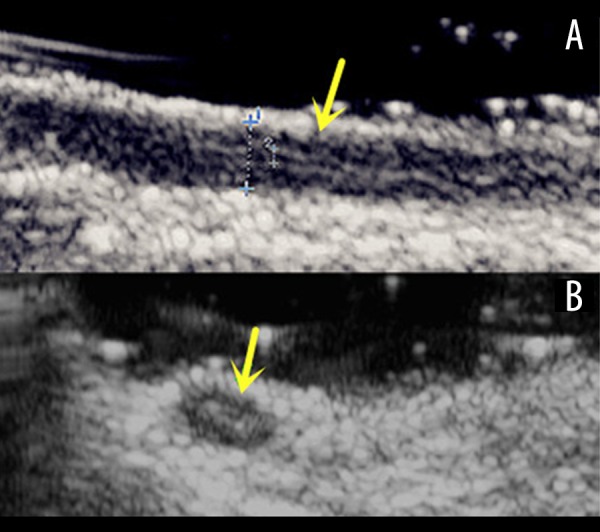

Five specimens from orchiectomy showed the ultrasonographic feature that was identical with the VDs in vivo before surgery and the diameter was also the same. The image of the VD was a cord-like structure with 2 parallel linear reflectors representing the internal walls of the lumen surrounded by a thick, hypoechoic, and mostly muscular wall in the longitudinal plane. In the transverse plane, the VD showed a “target-like” appearance (Figure 1).

Figure 1.

Image of the spermatic cord specimen and evaluation of the VD in the spermatic cord. (A) Longitudinal view of the VD shows its lumen and thick hypoechoic wall (arrow). (B) Transverse view of the VD shows its “target-like” appearance (arrow).